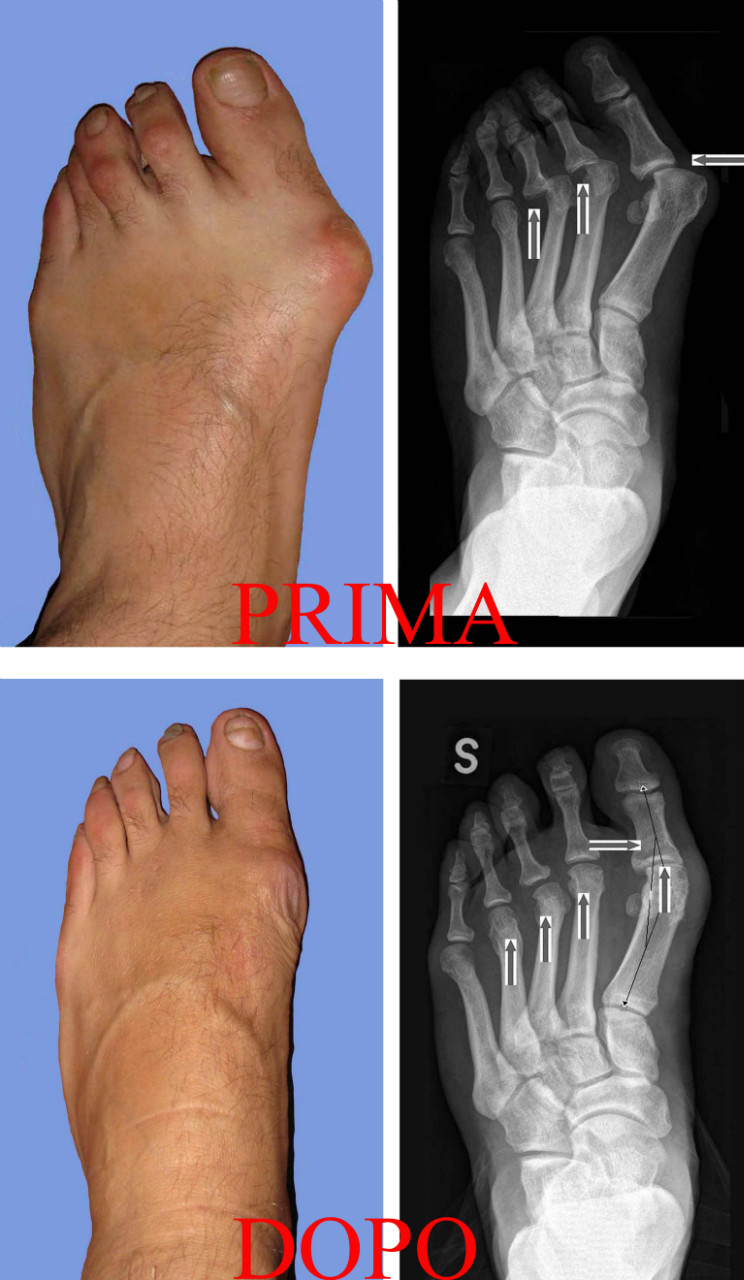

L’Alluce valgo è una deformità del piede che consiste in un’inclinazione dell’alluce (il primo dito del piede) verso le altre dita con la contemporanea deviazione del primo osso metatarsale ( che si articola con l’alluce) verso l’interno. Si crea quindi una deformità a zig zag che accorcia ed allarga il piede e determina la tipica sporgenza ossea chiamata esostosi o più comunemente “cipolla” la quale provoca una serie di non trascurabili conseguenze come arrossamento, dolore, infiammazioni (borsiti) e talvolta ulcerazioni, e rende sempre più difficile camminare normalmente ed indossare calzature di qualsiasi genere.

Molto importanti per la valutazione accurata di tale patologia sono le radiografie che devono essere sempre effettuate con il paziente in posizione sotto carico, gli esami di base devono includere le proiezioni dorso-plantare e laterale, che permettono di quantificare l’ampiezza in gradi della deviazione ossea ( angolo Intermetatarsale e Metatarso-Falangeo, PASA, DASA, TASA) e la proiezione di Walter Muller per un accurata valutazione dei sesamoidi (due piccole ossa sotto l’articolazione Metarso-Falangea.

Sono state messe a punto più di 100 tecniche chirurgiche per l’alluce valgo, dalle più obsolete come quelle che si limitavano a togliere la “cipolla” e ritensionare i tessuti “allentati” o demolivano l’articolazione Metatarso-Falangea e con gravi conseguenza sulla dinamica del passo con lunghe e dolorose degenze post-operatorie, alle più moderne che hanno lo scopo di conservare l'articolazione e correggere le deformita' mediante osteotomie ("fratture" create artificialmente) che permettono di dare un corretto orientamento alle ossa del metatarso e delle falangi in modo da correggere gli angoli alterati ed ottenere un restringimento trasversale dell'avampiede .

Le osteotomie possono essere distali, diafisarie e prossimali, associate ad interventi sulle parti molli come tendini e legamenti per poter meglio centrare l'alluce nella sua corretta posizione.

Quindi è bene precisare che non esiste un solo intervento per tutti gli alluci valghi. Ogni alluce valgo presenta delle sue peculiari caratteristiche che vanno valutate con la visita medica e gli esami radiografici ed in base a queste deve essere scelto l’intervento più adeguato.

Si tratta di una tecnica percutanea ossia attraverso dei buchini della cute, e sotto il controllo di uno strumento radiologico (amplificatore di brillanza o fluoroscopio), il chirurgo manovrando delle minifrese, simili al trapano del dentista, può eliminare la dolorosa prominenza (esostosi) e, tramite delle osteotomie, riallineare l´alluce, correggere le metatarsalgiee e le dita a martello.

Tale tecnica può essere utile però, solo in quei casi di deformità medio-grave, circa il 60-70% dei casi; nei restanti attuiamo tecniche miste percutanea-cielo aperto sempre di ultima generazione che però prevedono l’uso di mezzi di sintesi (viti, fili metallici). Si tratta di tecniche dette triplanari (tra cui la Chevron modifica Johnson e la Scarf ) le quali permettono di spostare il metatarso in tre direzioni per meglio correggere l´alluce e ripristinare la funzione.